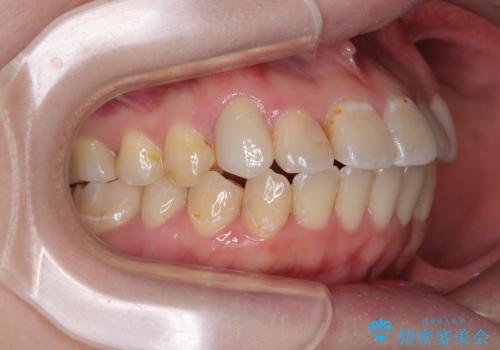

- 上下の歯が非接触であり、八重歯やむし歯を気にして来院された患者様です。

下顎骨の左右偏位はあるものの、上顎骨幅が相対的に狭い状態であったので、奥歯の咬み合わせが非常に乱れていました。

急速拡大装置により上顎骨幅を側方に拡大し、それを利用して八重歯を歯列に納めることにしました。

急速拡大が奏効し、非抜歯矯正にて八重歯を解決することができました。